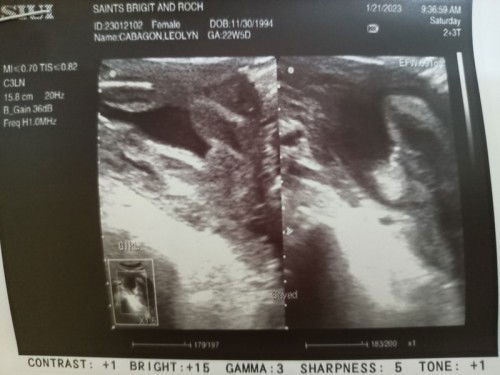

Gender Ultrasound

Mga mommy sa tingin nio po baby girl po ba talaga eto? ☺️☺️23 weeks preggy po ako. Thank you.